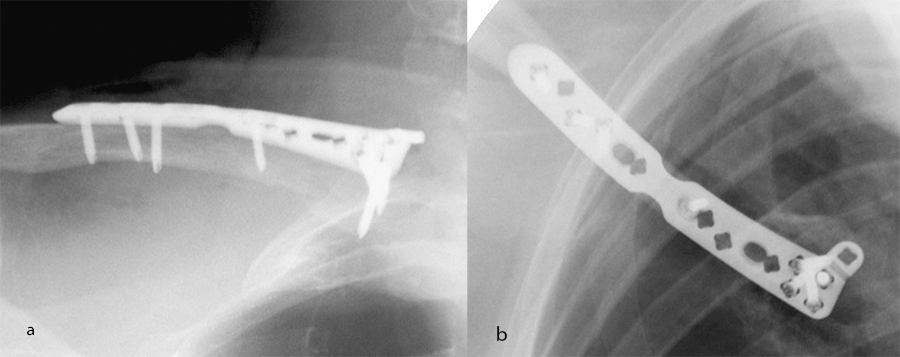

A 54-year-old man sustained a mid-shaft fracture to his right clavicle following a 2 m fall from a ladder (Fig 13). Intraoperative images show plate placement and screw insertion (Fig 14). Postoperative image depicting minimal incision size for plate insertion before wound closure (Fig 15). Image shows the fracture healing at 6 weeks’ follow-up (Fig 16).